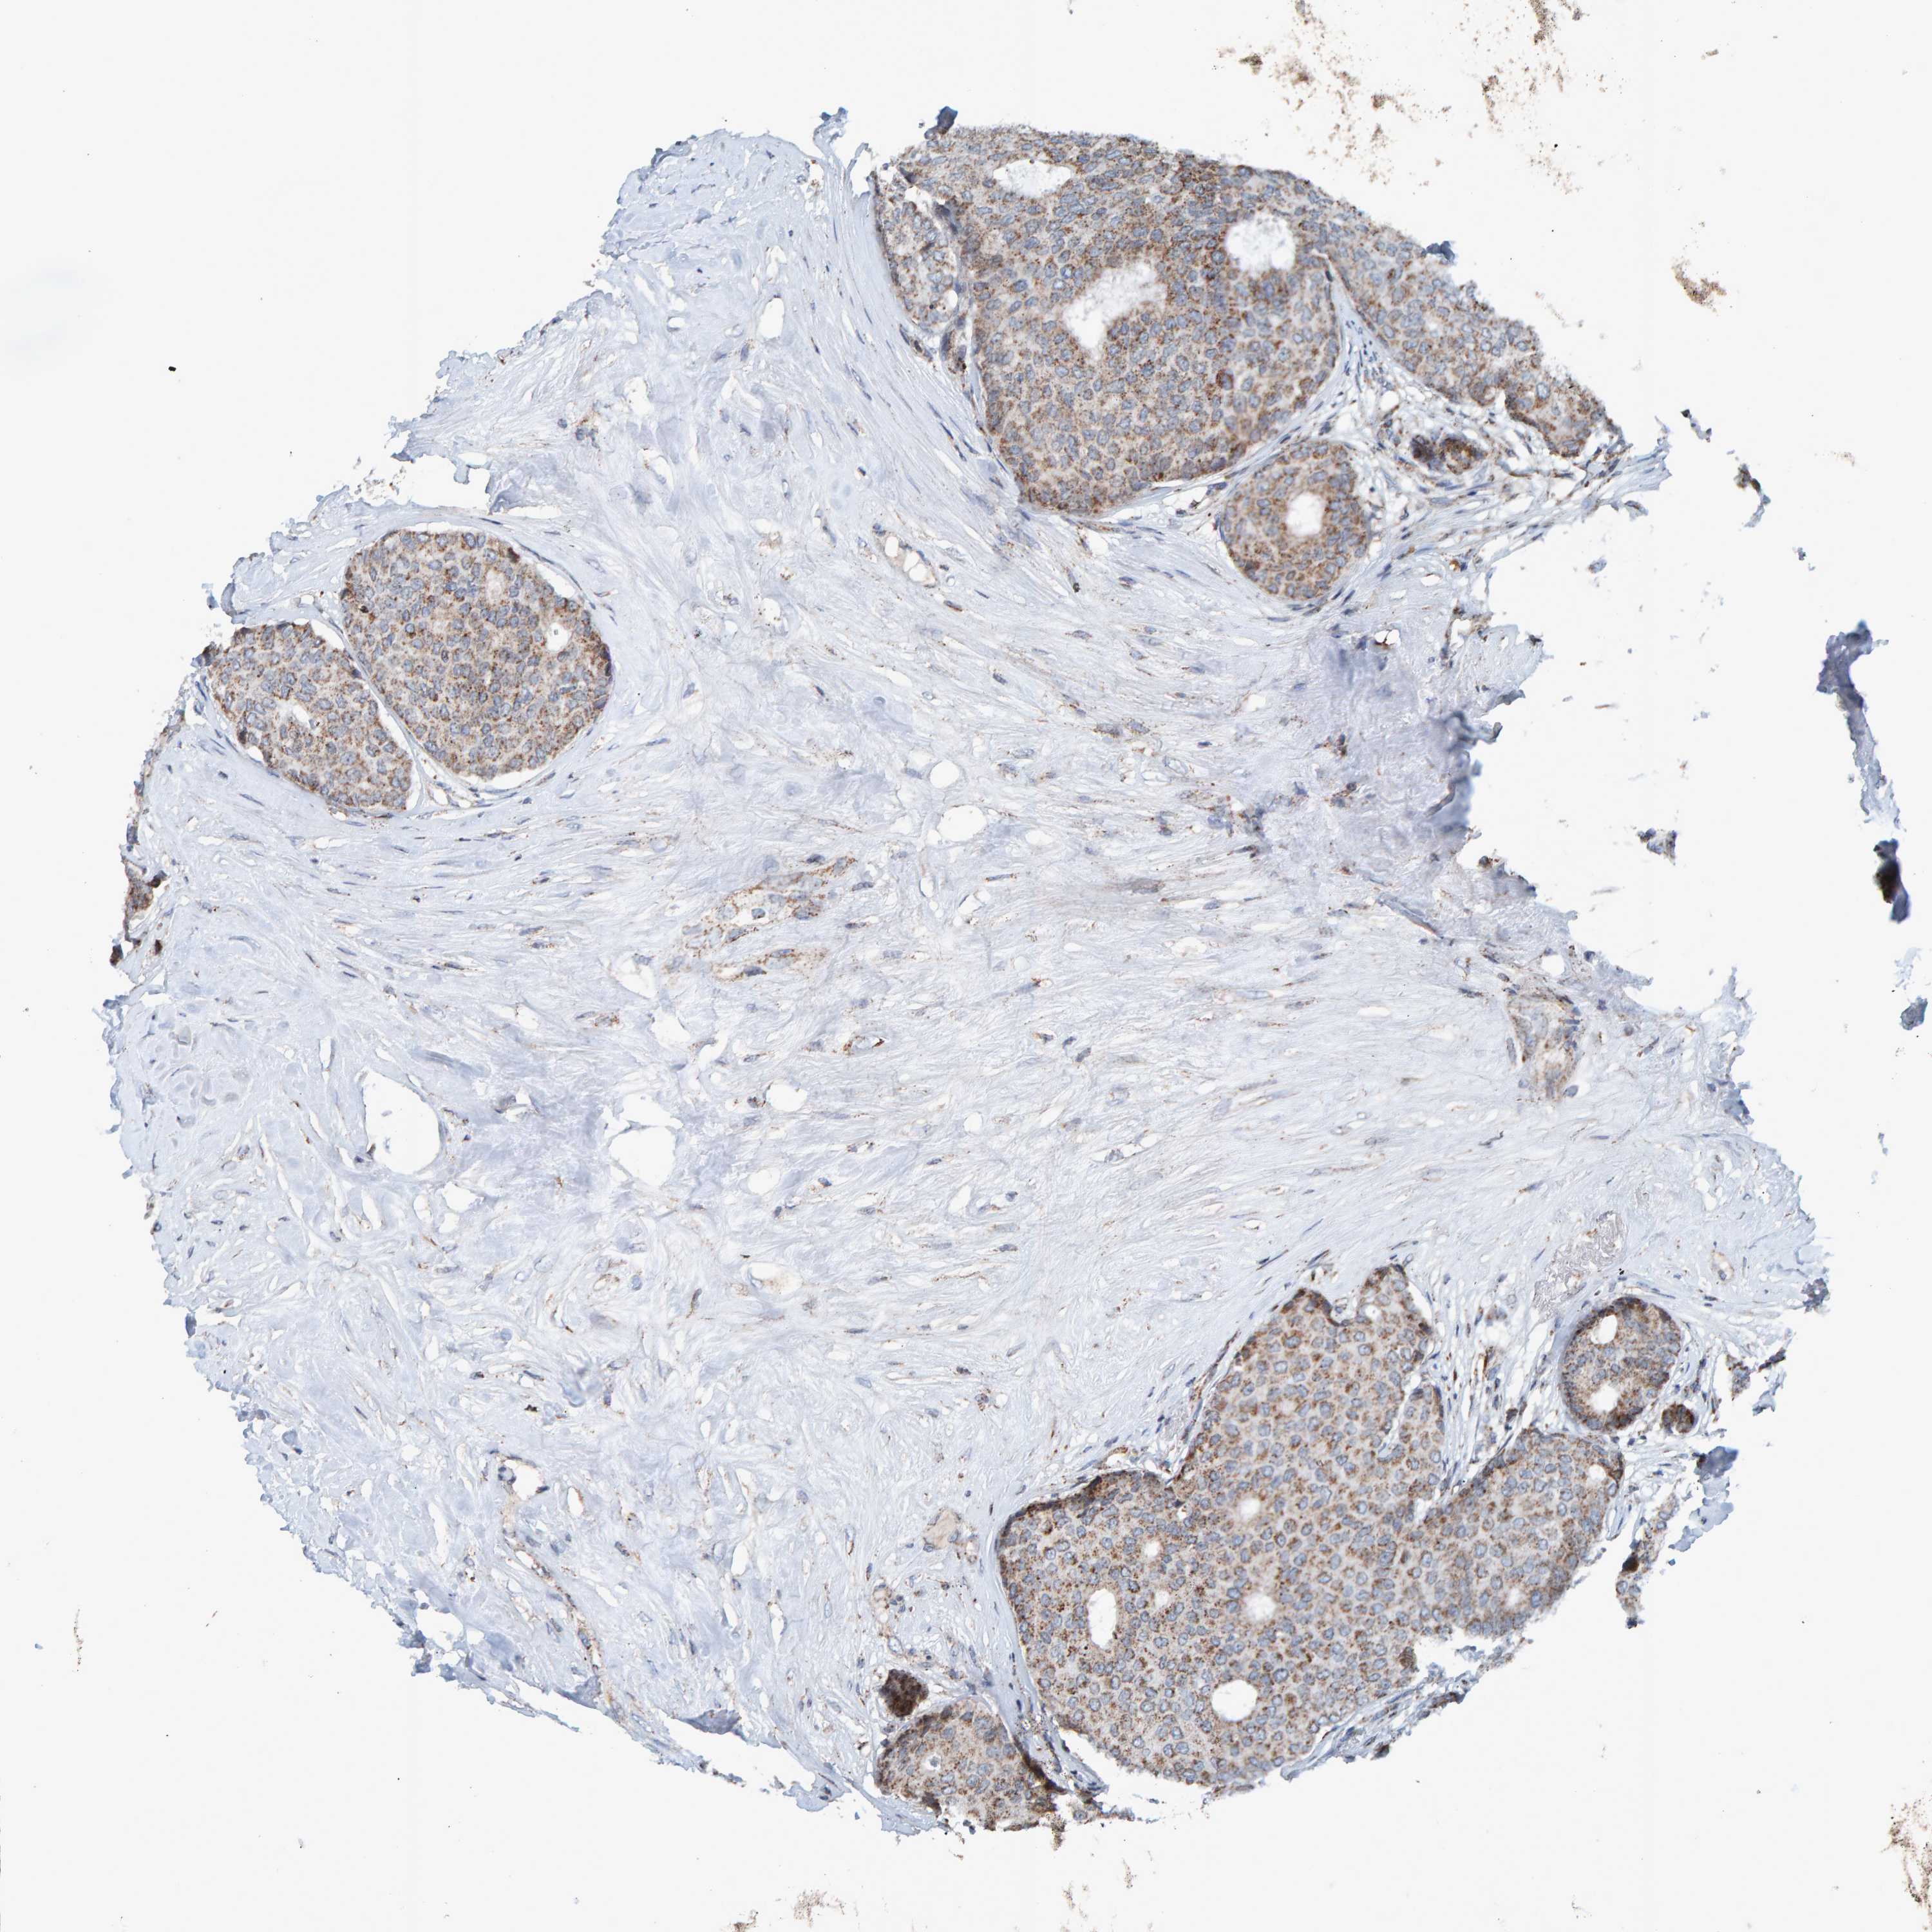

CANCER BREAST CANCER Show tissue menu

BRCA TCGA BRCA VALIDATION PROTEIN EXPRESSION